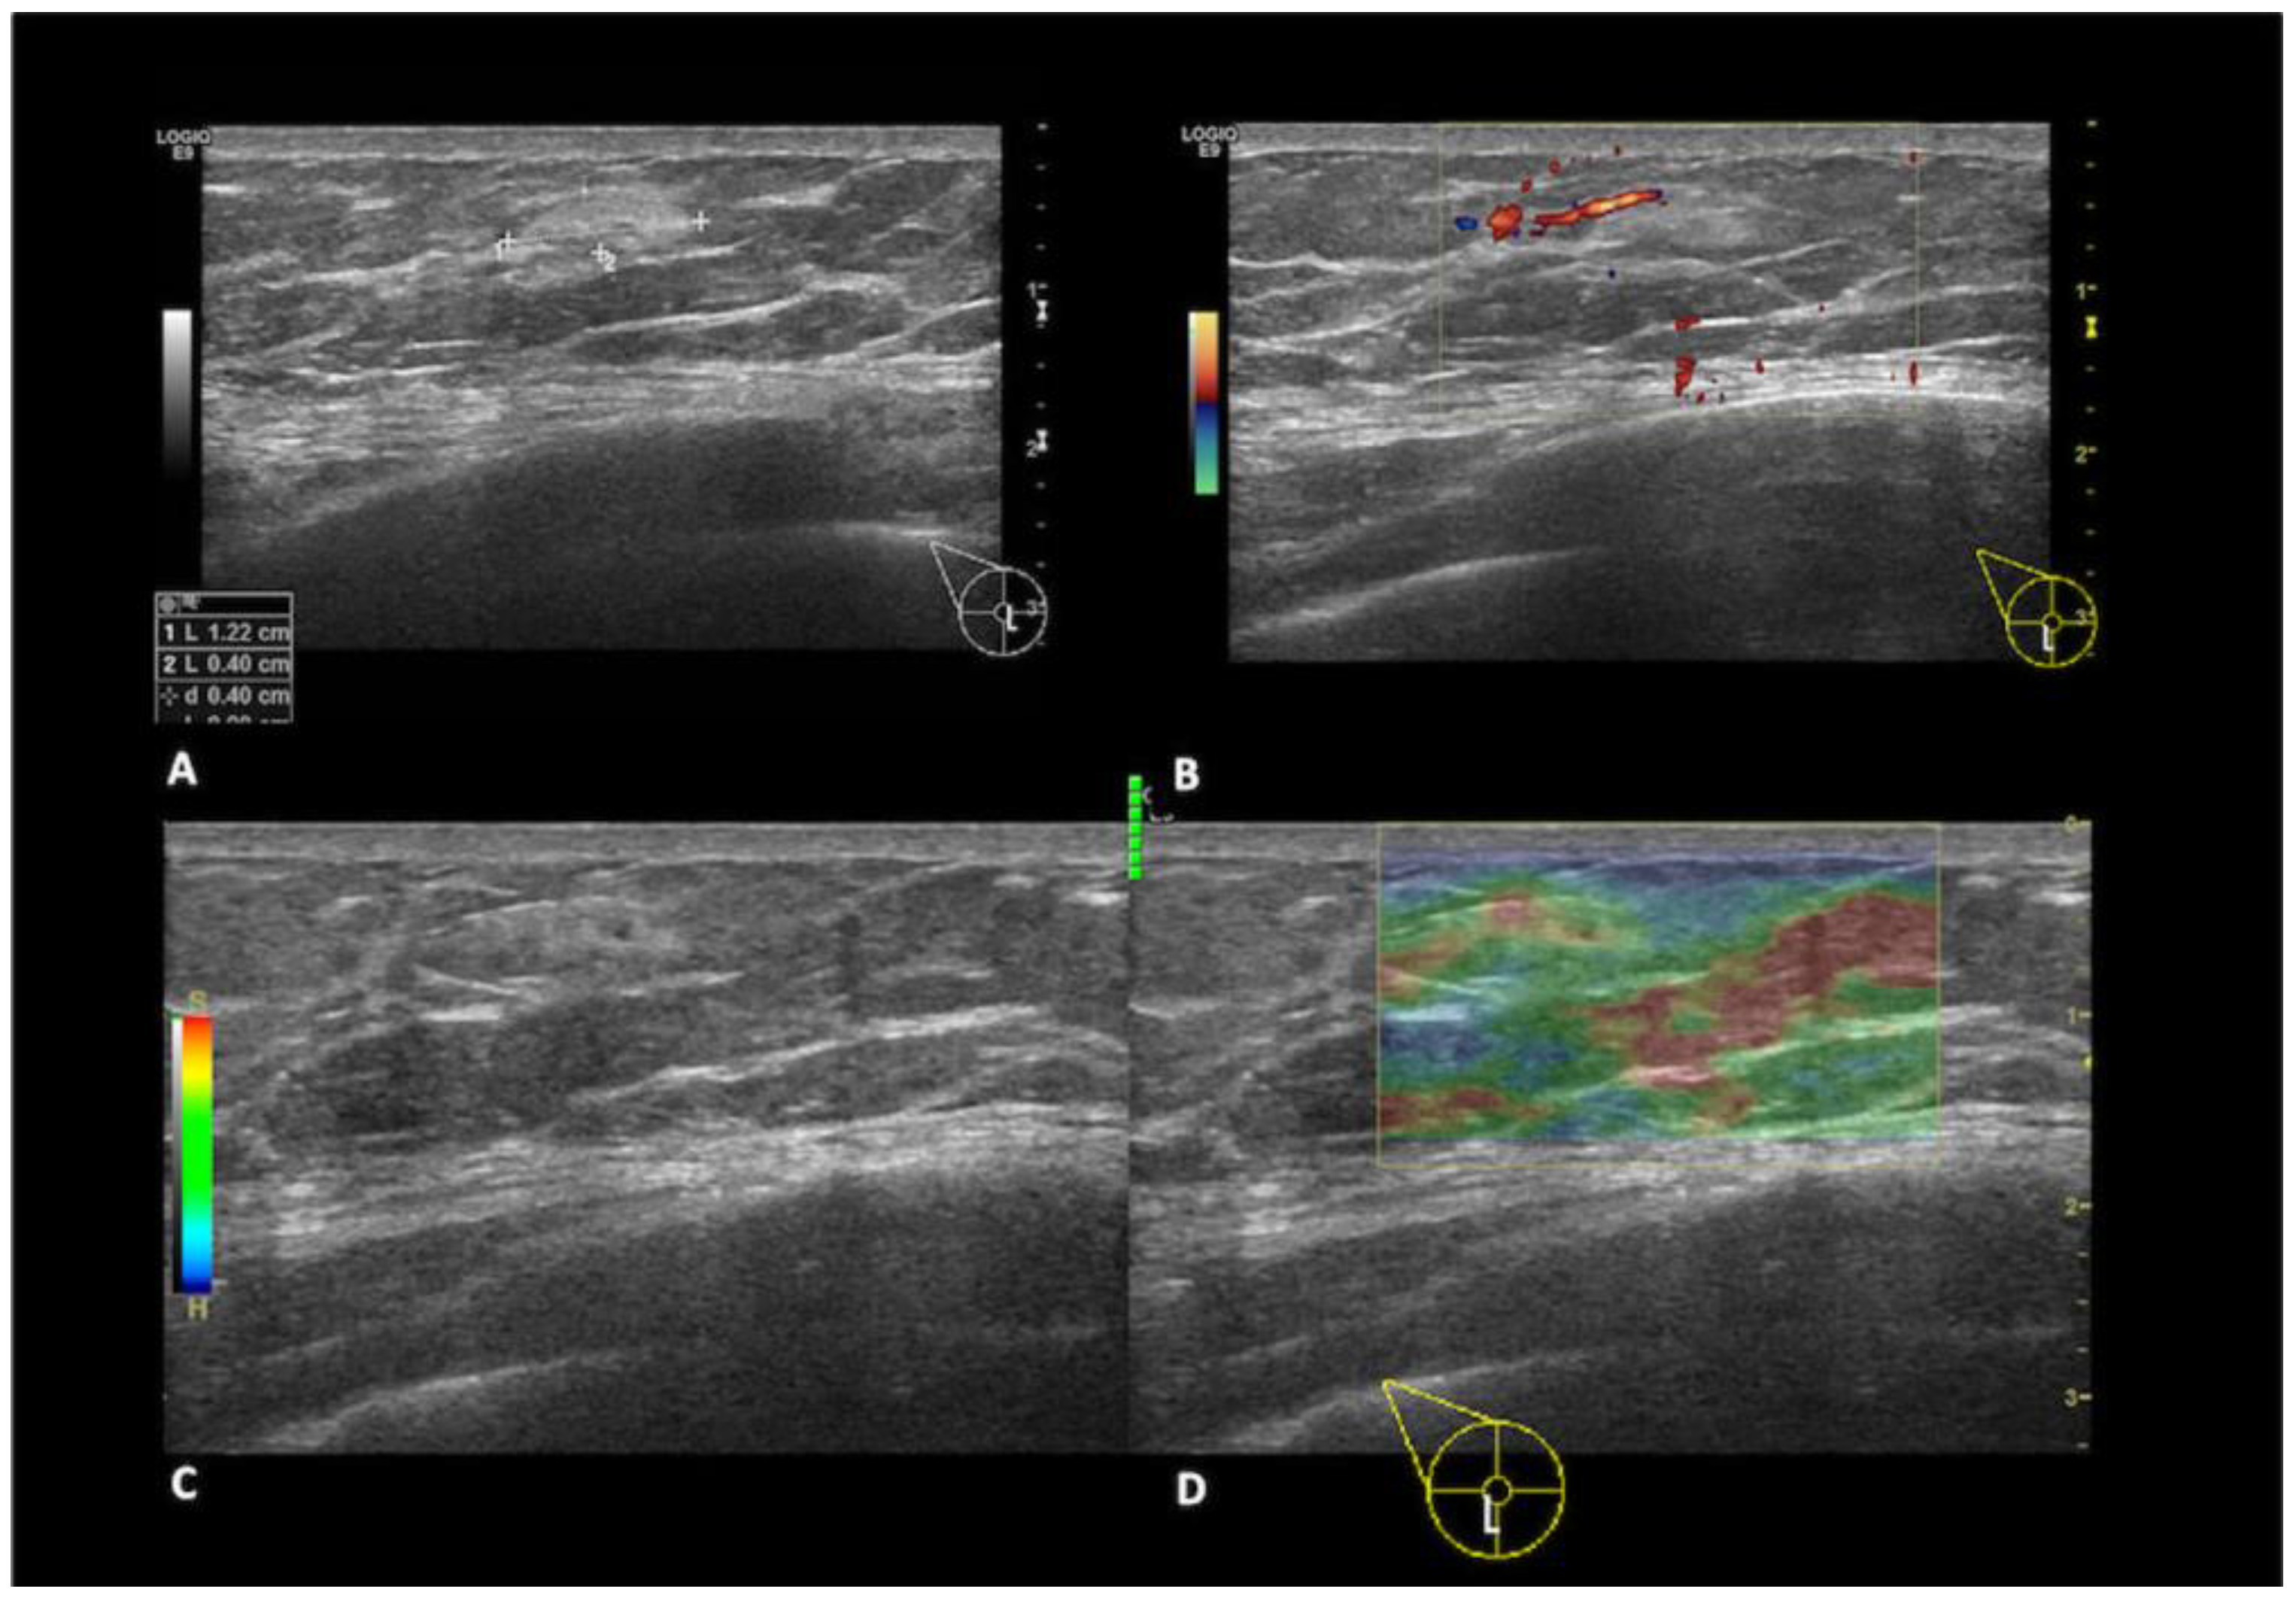

Lipomas, the second most common benign lesions in the MB, are composed of adipose tissue and typically present as soft, mobile, and palpable masses in clinical examination. However, they are frequently detected incidentally. Mammographically, lipomas appear as well-defined radiolucent oval masses with a radiopaque capsule that might be difficult to detect [14,15]. On ultrasound, lipomas demonstrate an oval shape, parallel orientation, iso-hyperechoic echogenicity, and lack detectable vascular flow [16] (Figure 3).

Figure 3.

A 35-year-old men with a palpable lump in the inner quadrants of the left breast. On a B-mode (A) breast ultrasound, there is an oval shaped and hyperechoic mass, with circumscribed margins and parallel orientation. No posterior feature is associated. On color-doppler (B), there are no signs of vascularization. The imaging features are consistent with a lipoma.